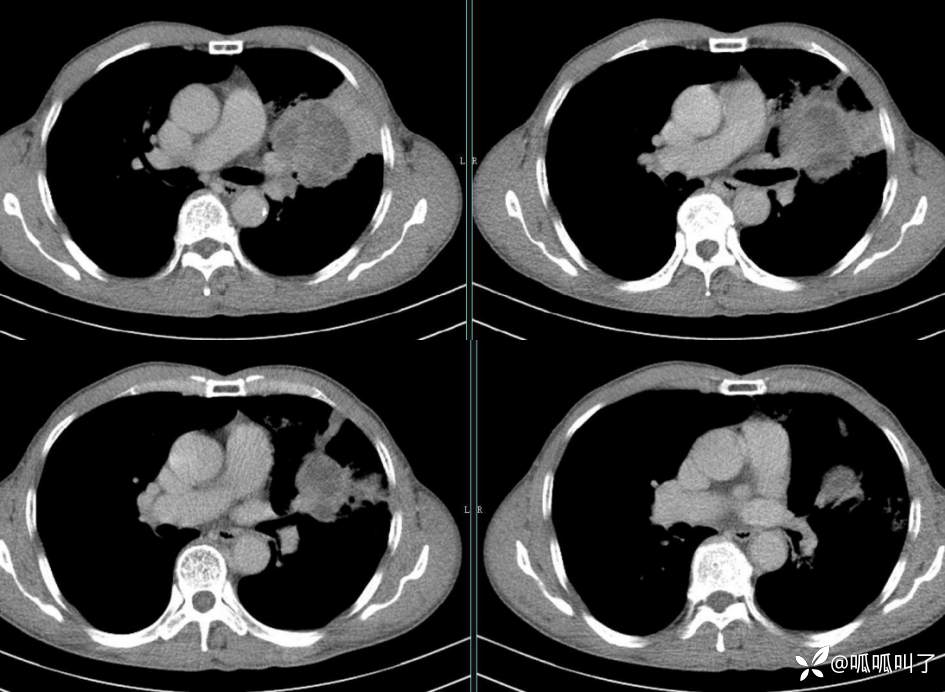

胸部CT平扫和增强: